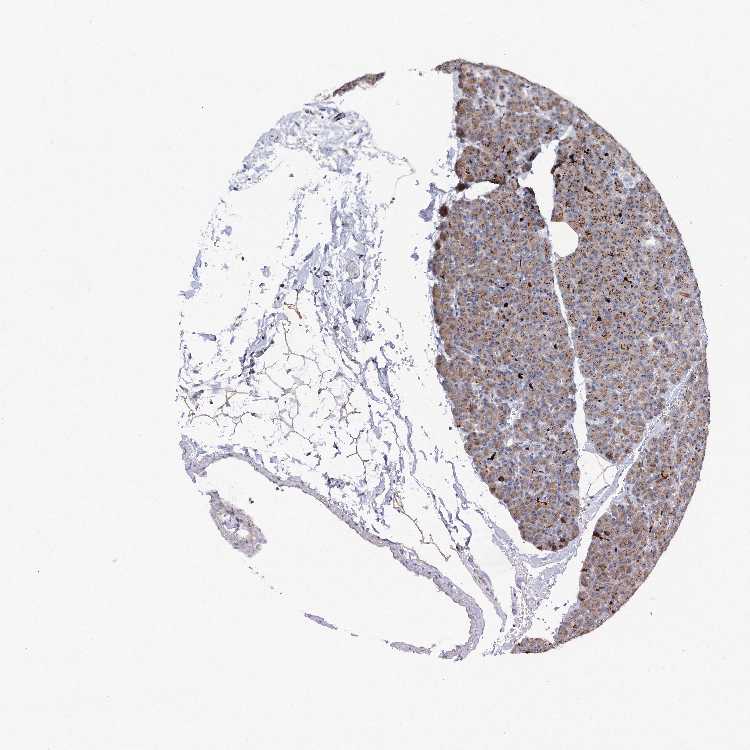

PANCREAS - Antibody stainingi

Antibody staining in the annotated cell types in the current human tissue is reported as not detected, low, medium, or high, based on conventional immunohistochemistry profiling in selected tissues. This score is based on the combination of the staining intensity and fraction of stained cells.

Each image is clickable and will lead to virtual microscopy that enables deeper exploration of all samples and also displays staining intensity scores, fraction scores and subcellular localization as well as patient and tissue information for each sample.

Antibody HPA038793Antibody HPA053691

Exocrine glandular cells MediumMedium

Pancreatic endocrine cells Not detectedNot detected